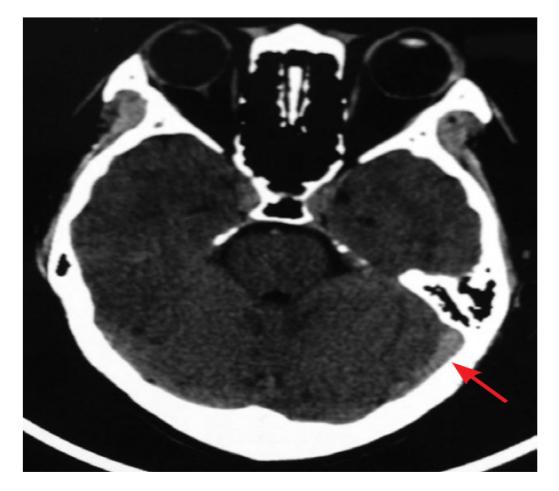

(2)病变部位及病因:病变部位可以原发于脑内浅静脉、深静脉或静脉窦,其中深静脉血栓以大脑大静脉及大脑内静脉为主,单纯浅静脉血栓也比较少见,多同时合并静脉窦血栓。多数患者同时累及多个静脉窦,其中以上矢状窦为主,横窦、乙状窦及直窦血栓也比较常见。

图1 MRV提示静脉系统结构及静脉血栓形成发病率(3)临床表现:约90%患者出现头痛,40%患者伴有痫性发作,围生期比例甚至高达76%。患者多出现单侧或双侧,甚至是左右交替出现神经功能缺损。20%患者入院时出现意识障碍,为预后不良的强烈预测因素。